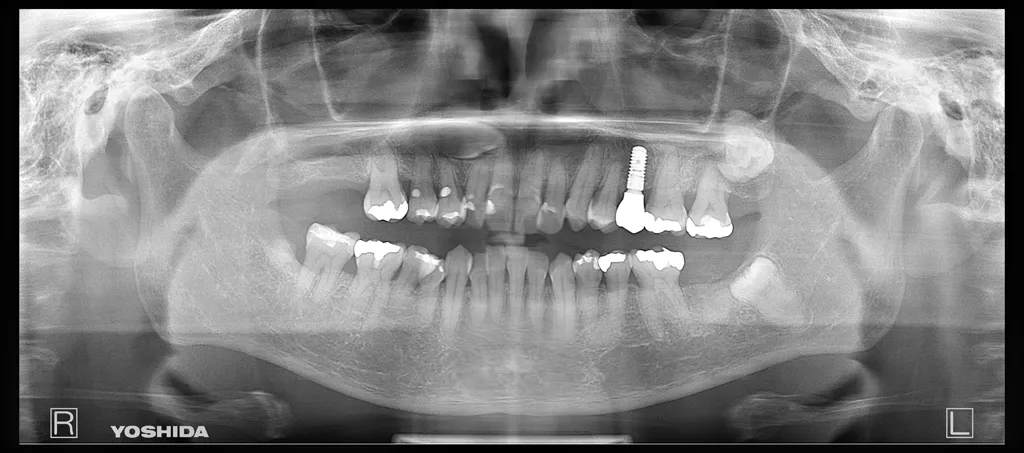

インプラントの症例

54歳 女性

歯が割れていてインプラントを検討したい。

治療本数:1

治療部位:25

治療方法:抜歯即時埋入+GBR

種類: ITI(ストローマン)+ジルコニア

回数:3回

期間:4ヶ月

術後の腫れ、痛み、歯肉退縮、インプラント埋入位置の近接による天然歯の動揺、歯根吸収、知覚過敏、歯の変色、術中の血管/神経損傷による出血/麻痺、副鼻腔での感染および上顎洞炎等